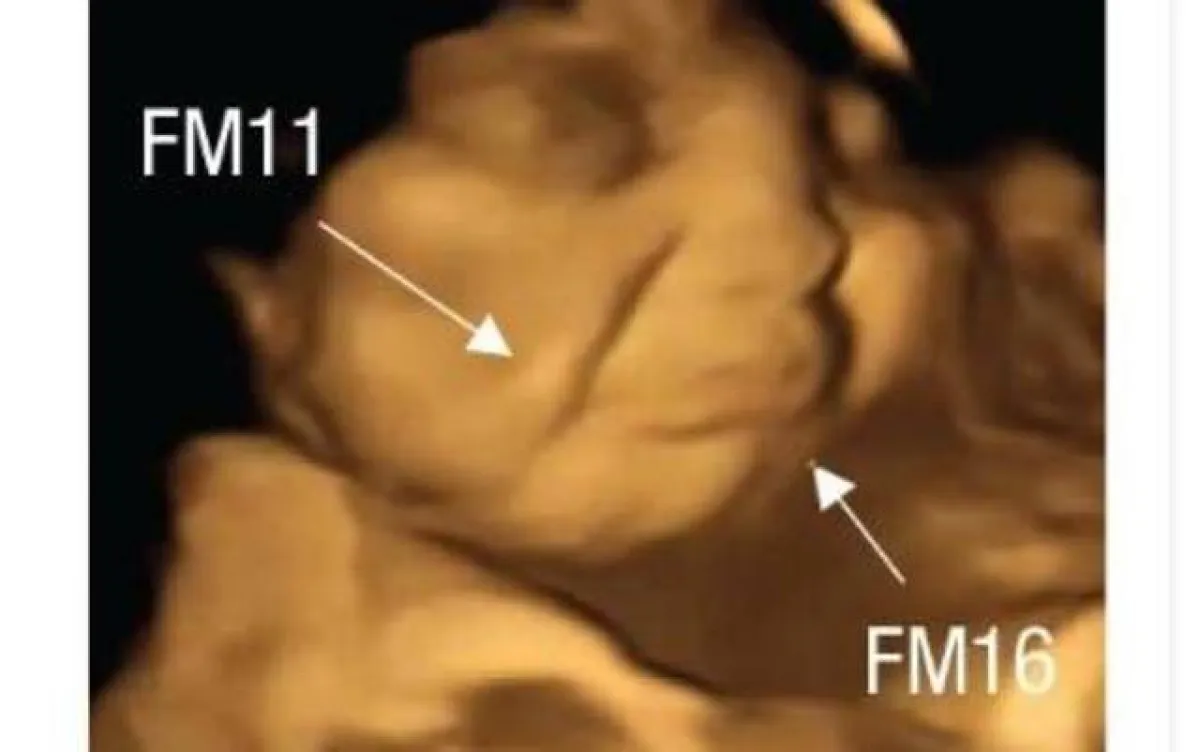

بعد فترة انتظار مدتها 20 دقيقة بعد الاستهلاك، خضعت النساء لفحوصات بالموجات فوق الصوتية رباعية الأبعاد، التي تمت مقارنتها بالصور ثنائية الأبعاد للأجنة. كان سحب زاوية الشفة، التي توحي بالابتسامة أو الضحك، أعلى بشكل ملحوظ في مجموعة الجزر مقارنة بمجموعة الكرنب والمجموعة الضابطة. في حين أن الحركات مثل رفع الشفة العليا، وإلقاء الشفة السفلية لأسفل، والضغط على الشفتين، ومجموعة من هذه الحركات -التي توحي بوجود وجه يبكي- كانت أكثر شيوعاً في مجموعة الكرنب من المجموعات الأخرى.